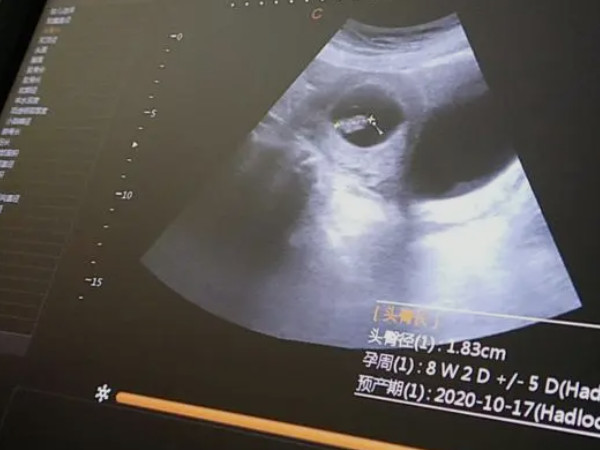

孕妇孕7周的时候,腹中的孩子已初具人形,能直接通过B超看到胚胎的四肢慢慢清晰。要知道,胎芽越占宫腔的三分之一,大概是1.33cm左右。此时可以通过胚芽的数据差和胎芽的形状来判断胎儿的性别。